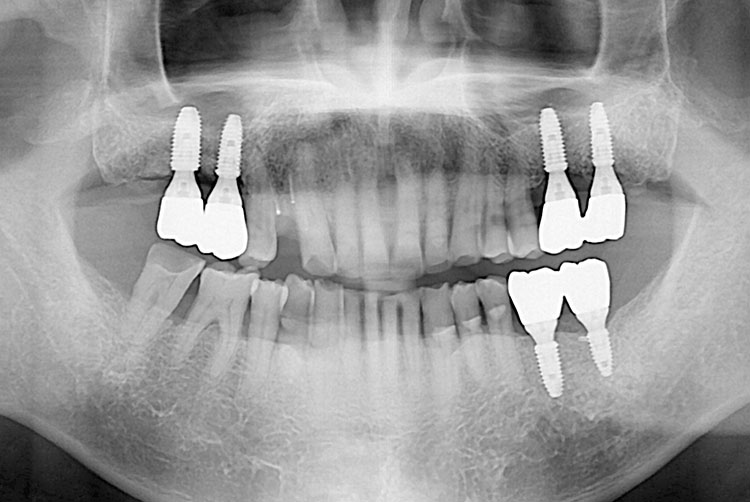

[임플란트] 임플란트

치료후 : 2019-08-29

세종치과는 많은 환자와 다양한 케이스를 바탕으로 항상 편안한 임플란트 수술을 제공하고자 노력하고,

오래동안 튼튼히 쓸 수 있는 임플란트 수술을 가장 큰 목표로 삼고 있습니다